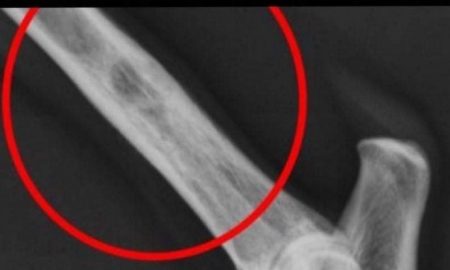

Istraživanja pokazuju kako se ova bolest godišnje dijagnosticira nekih 9.300 ljudi

Ova bolest je smrtonosna - evo koji sumptomi ukazuju na karcinom kostiju!